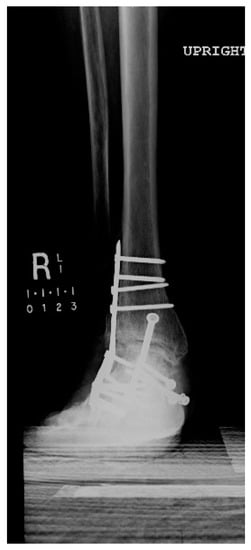

1.1.4. Post-Operative Imaging